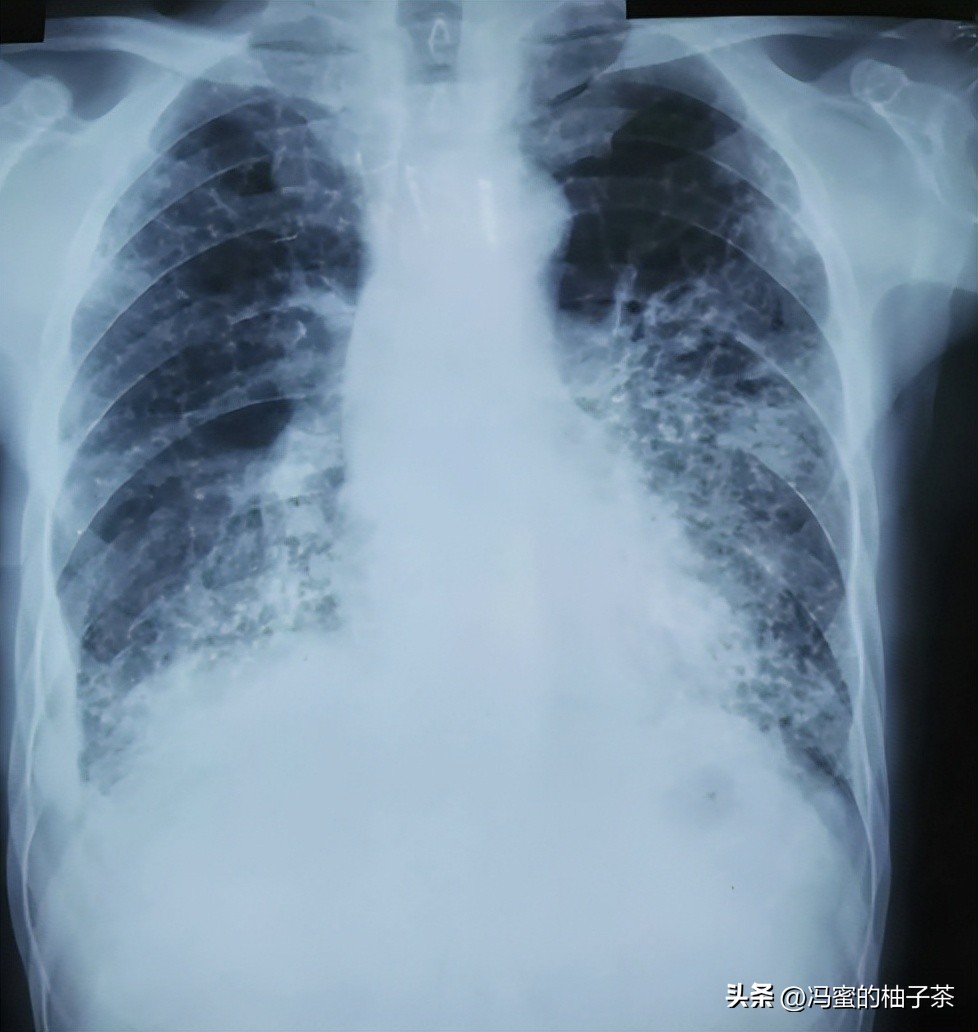

怕自己的身体也出现了问题,所以梁中南赶紧去医院做了检查。检查结果又给了梁中南重重一击,他生病了,得了尘肺病。

但好在尘肺病的治愈率很高,只要梁中南原理烟灰粉尘大的地方就会慢慢好转,治疗的费用也不高。

当初,要不是为了可小小治病,梁中南也不会拼命工作最后落得一个积劳成疾的下场。如今,再也不能干重体力活了,梁中南也就失去了经济来源,一家人的收入一下子少了一大半。